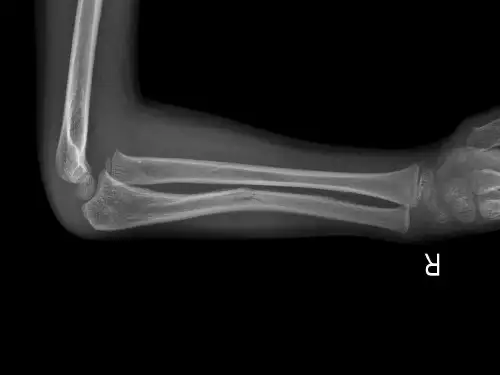

2.肘关节正、侧位X线片。

当尺骨上1/3骨折时,X片必须包括肘关节,注意肱桡关节解剖关系,以免漏诊。

孟氏骨折诊断与鉴别诊断诊断依据此种损伤的诊断一般无困难,除外伤史及临床特点外,主要依据正侧位X线平片所见。

四、孟氏骨折的诊断孟氏骨折的诊断主要依据临床表现和X线检查。

医生会对受伤手臂进行详细的体检,包括观察伤处是否有畸形、触摸骨折部位等。

此外,医生会安排X线检查以确定骨折的具体部位和类型。

拍摄X线片检查,一定不要只拍肘关节,应该包括前臂和腕关节。

在正常的肘关节X线片,沿着桡骨轴画一条线,这条线应该穿过桡骨头和肱骨小头的中心。

如果不是,应该高度考虑桡骨头脱位。